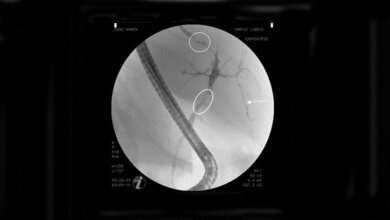

Desmosomen sind knopfartige Strukturen in Zellmembranen, die dazu dienen, benachbarte Zellen fest aneinander zu binden. Man findet sie vor allem in Zellen und Geweben, die einer hohen mechanischen Belastung ausgesetzt sind, beispielsweise in der Haut. „Bei PV werden diese Strukturen durch körpereigene Antikörper angegriffen, so dass die Adhäsion von Hautzellen – die Keratinozyten – und Zellen der Schleimhäute verloren geht“, erläutert Prof. Tikkanen. Die Biochemikerin ergänzt, dass dies zur Bildung von Blasen und Läsionen führe: „Für die betroffenen Patientinnen und Patienten kann das unter Umständen lebensbedrohliche Auswirkungen haben.“